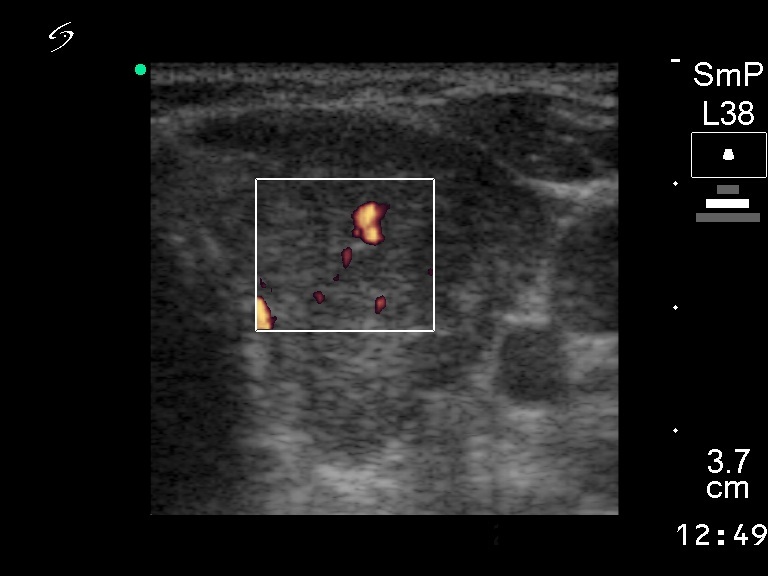

Ultrasonography: there was a hypoechogenic nodule in the left lobe. The nodule displayed coarse calcification and a type 3 vascular pattern.